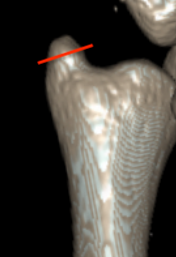

Classification ulna styloid fractures

| Type 1: Tip | Type 2: Base | Type 3: Proximal to styloid |

Operative management

Indication

DRUJ instability after distal radius ORIF with ulna styloid fracture

Techniques

Options

Styloid screw

Tension band wire

Ulna hook plate